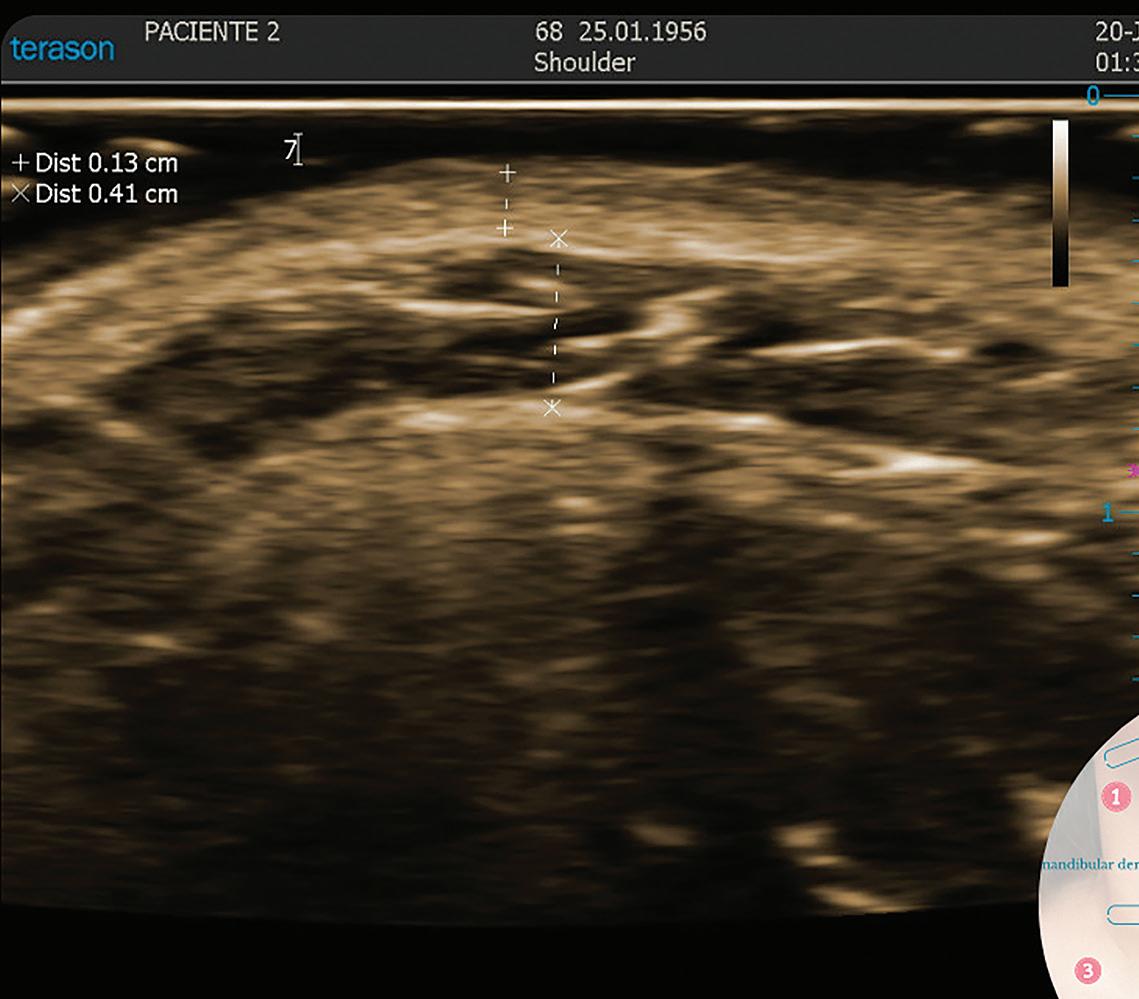

Five female patients underwent three monthly sessions of Bellacholine (LG Chem Ltd., Korea) injections (2 ml per session) using a 29G x 12.7mm, 30G x 38 mm needle. Realtime ultrasound-guided dosing and measured fat thickness. 2D photography and 3D surface imaging were used to assess visual and volumetric changes. Among the five, three representative cases were selected for detailed analysis.

Bellacholine, a deoxycholic acid-based injectable designed to selectively break down adipocytes, was administered in three sessions at one-month intervals. Each session involved a 2 ml injection using 29 G x 12.7 mm, 30 G x 38 mm needle. The injection was performed using a linear technique at 2–3 points per side in the submental region. Real-time ultrasound (ECUBE 8, Alpinion, Seoul, Republic of Korea) was used to assess fat thickness and guide

■ Real-time ultrasound imaging (ECUBE 8): Ultrasound was used to measure submental fat thickness at baseline and at the final follow-up. Measurements were taken at standardised anatomical landmarks to ensure consistency across sessions.

Ultrasound measurements

Submental fat thickness was measured using real-time ultrasound at baseline and at the 11-month follow-up. All three patients showed a consistent reduction in fat layer thickness:

Ultrasound measurements of patients baseline and 11-month after Bellacholine treatment

Figure 1 Submental fat thickness reduction (ultrasound)

These reductions indicate the adipolytic effect of Bellacholine, as evidenced by visible thinning of the preplatysmal fat layer.